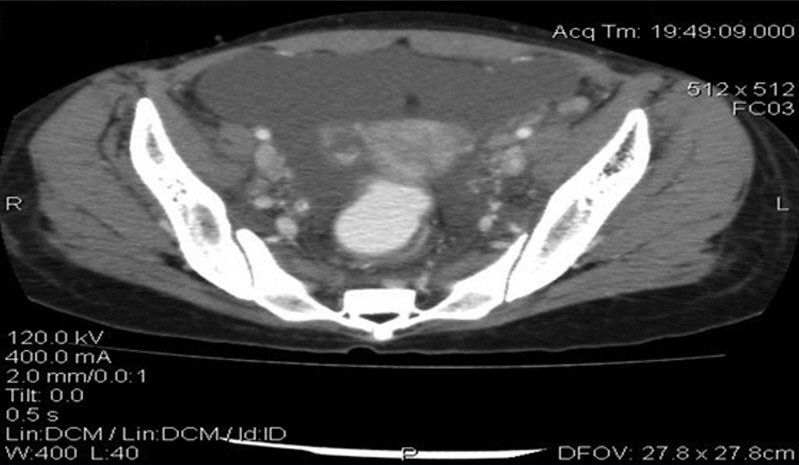

癌胚抗原(CEA)水平正常,但CA-125水平升高为93.5μg/ml(正常范围,0~35μg/ml)。进行腹部和盆腔的CT扫描,证实存在中度腹水和腹膜结节(图2)。膀胱壁和肠壁增厚(图3)。双侧肾积水和多个扩大的主动脉旁淋巴结也可见(图4)。

图2 盆腔增强CT显示盆腔游离液体